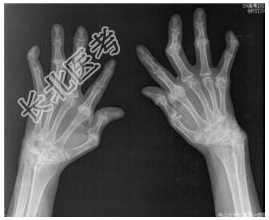

- [材料题] 患者女,55岁,全身多处关节肿痛30余年。查体:双手关节多处变形,晨僵,类风湿因子阳性。行双手正斜位片检查。

- 简答题1、患者的诊断及依据是什么?

- 简答题2、鉴别诊断是什么?